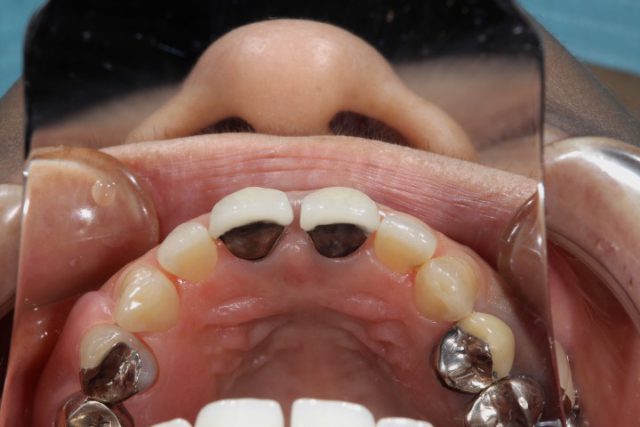

施術後

術後の画像です。前歯の隙間もしっかりと無くなり解消されています。周りの歯との色も自然です。被せ物の付け根はどうですか?被せ物だとはほとんど分からなくなっています。歯の裏面もオールセラミックによる施術では白くなりますのでほとんど被せ物だということは分からなくなります。